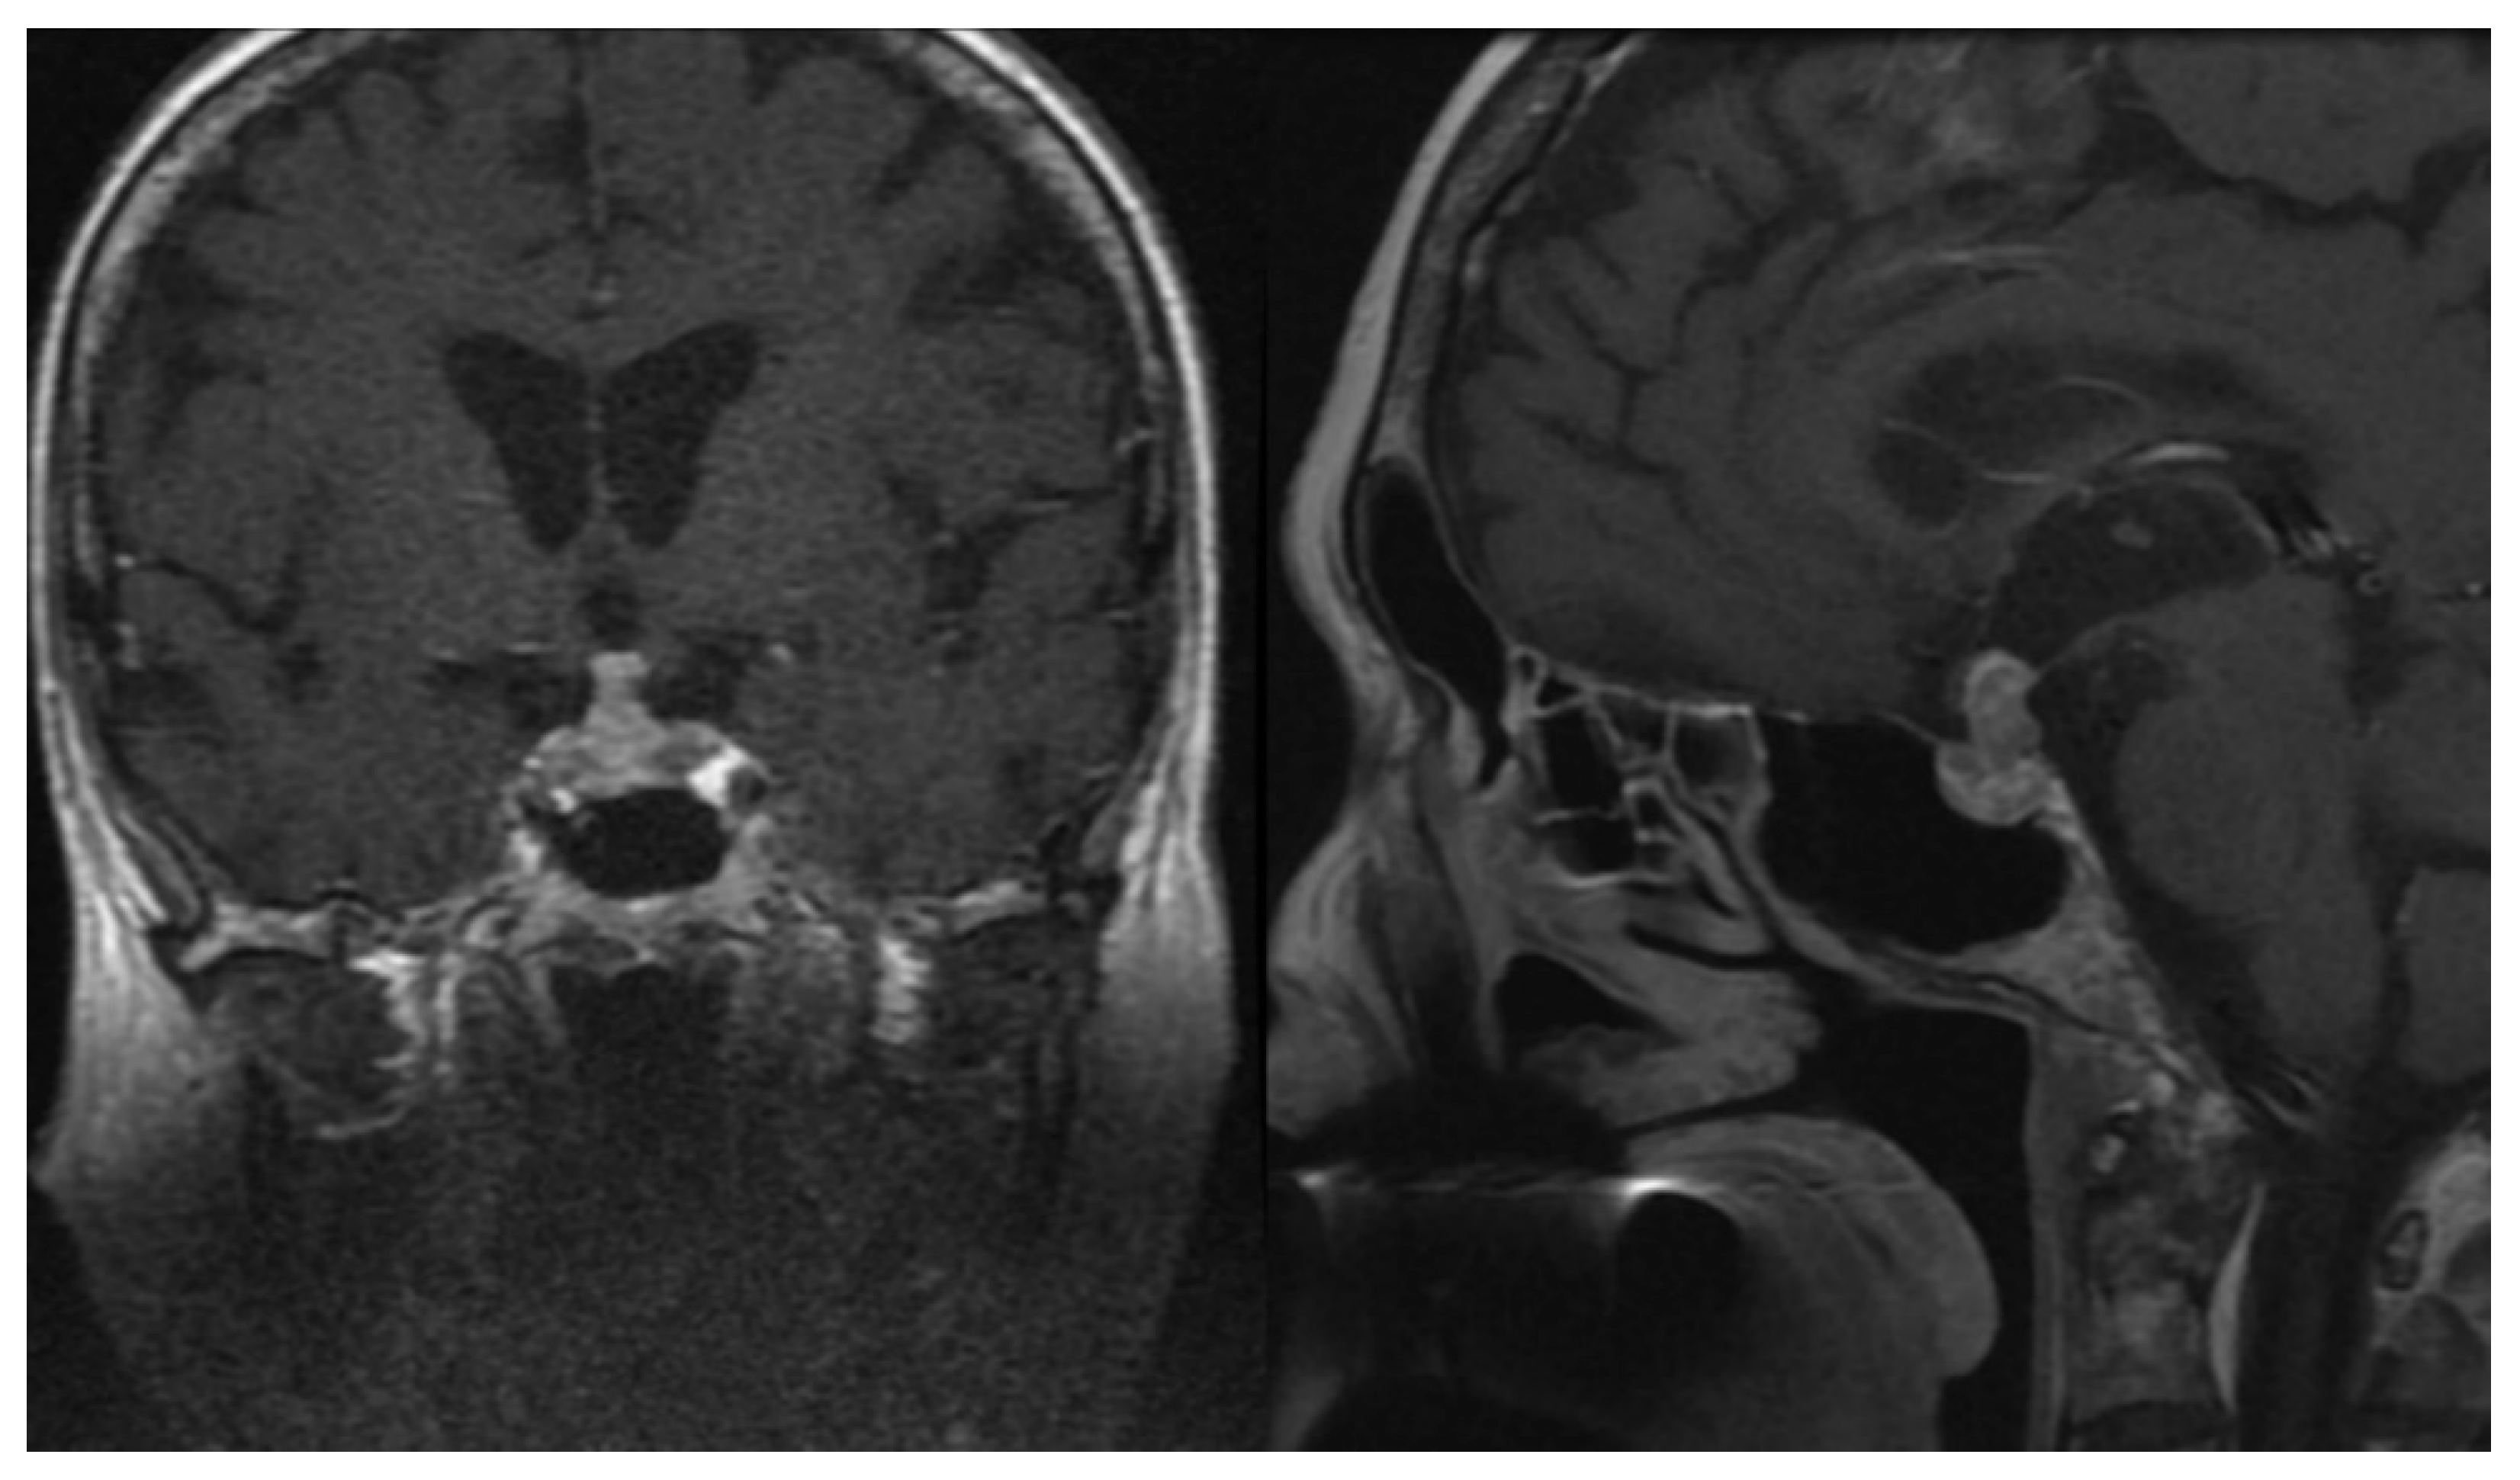

3.3. Neoplastic Change

3.4. Imaging